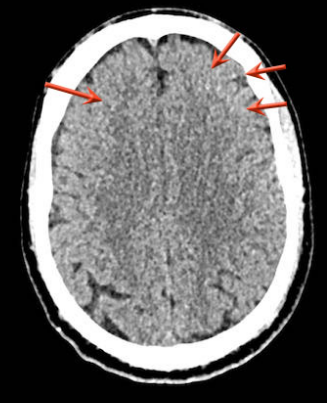

下图一例硬膜下血肿,很难发现(箭头)。

注意,在较高的水平上有双侧硬膜下血肿。